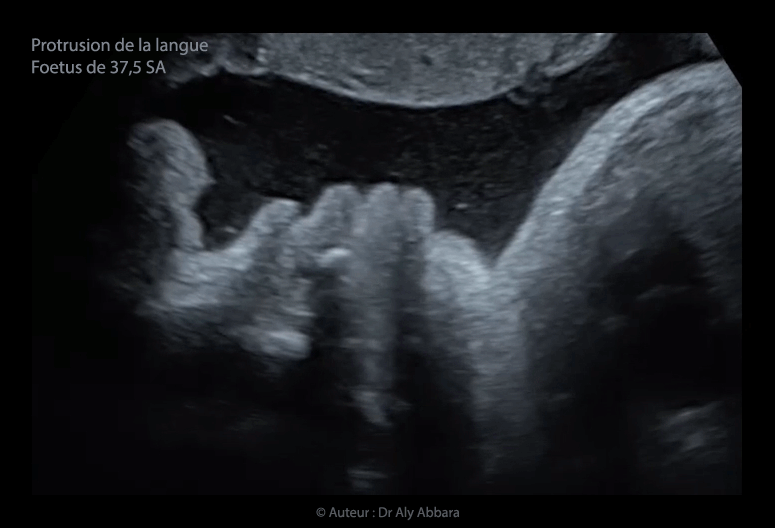

Protrusion de langue (aspect de 3 lèvres) - 37,5 SA

• Vidéo et images échographiques en 2D et 3D, à 37,5 SA montrant la présence d'une protrusion permanente de la langue (signe de 3e lèvre) ou l'interposition de la langue entre les deux lèvres en rapport avec une macroglossie.

Il s'agit, chez ce fœtus, d'un signe échographique isolé ; la morphologie et la biométrie fœtales sont par ailleurs normales et en enfin, le nouveau-né est sans anomalie particulière.

• On parle de la protrusion de la langue ou l'interposition constante de la langue entre les deux lèvres (signe de 3e lèvre sur la coupe sagittale médiane de la face), quand, au cours de l'examen échographique, le bout de la langue se trouve en permanence en avant de l'arcade alvéolaire dentaire des maxillaires inférieur et supérieur.